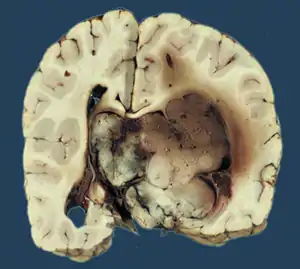

Choroid plexus papilloma

Choroid plexus papilloma, also known as papilloma of the choroid plexus, is a rare benign neuroepithelial intraventricular WHO grade I lesion found in the choroid plexus.[1] It leads to increased cerebrospinal fluid production, thus causing increased intracranial pressure and hydrocephalus.[2]

| |